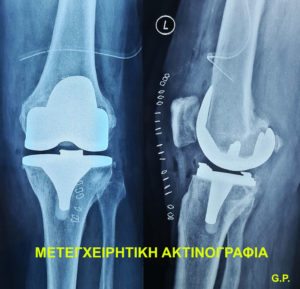

Ολική αρθροπλαστική γόνατος ονομάζεται η χειρουργική επέμβαση, στην οποία γίνεται αντικατάσταση της φθαρμένης άρθρωσης του γόνατος, από μία τεχνητή άρθρωση, που αποτελείται από 3 μέρη. Το ένα αντικαθιστά τον φθαρμένο χόνδρο του μηριαίου, το δεύτερο το φθαρμένο χόνδρο της κνήμης, ενώ ανάμεσα στα 2 παραπάνω εμφυτεύματα τιτανίου, παρεμβάλλεται μία φέτα πολυαιθυλενίου (πολύ ανθεκτικού πλαστικού).  Είναι από τις συχνότερες ορθοπαιδικές επεμβάσεις που διεξάγονται, γιατί αφορά ασθενείς με οστεοαρθίτιδα, τραυματική αρθρίτιδα, ρευματοειδή αρθρίτιδα, άσηπτη νέκρωση και όγκους. Τον τελευταίο καιρό, γίνεται πολύς λόγος για τις μεθόδους διεξαγωγής της επέμβασης, το χρόνο νοσηλείας, το κατάλληλο νοσηλευτικό ίδρυμα και άλλα πολλά.